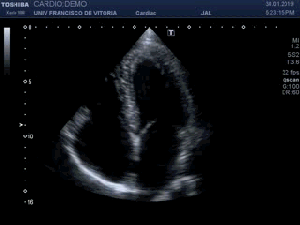

139. Ecocardiografía. Estudio Paraesternal Eje Largo.

142. Ecocardiografía.Plano Apical 4 cámaras